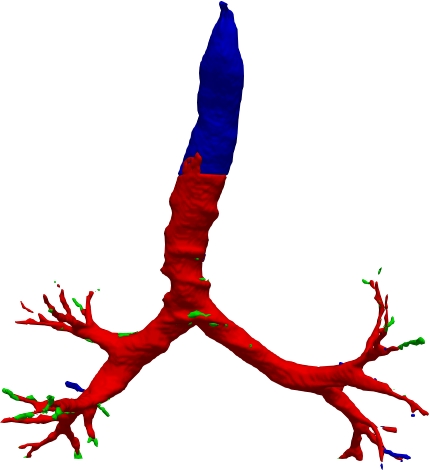

However, current state-of-the-art methods of lung organ segmentation still face several challenges and aspects for improvement. Firstly, the unlimited voxel values, multi-site imaging discrepancy and class imbalance in lung organ images can lead to false-negative and leakage issues in prior segmentation methods, which badly influences the critical early diagnosis of imperceptible lung diseases, e.g., lung fibrosis, nodule and hypertension, etc. Secondly, the presence of numerous slender branches, e.g., bronchioles and arterioles, which are easily lost during the recycled down/up-sampling procedure in Fig. 1, can result in discontinuity, detail loss, and coarse mask predictions. Thirdly, most CNN-based medical segmentation methods treat all points equally during the mask rendering stage, overlooking the vulnerability of border points in Fig. 1 (f) and the importance of explicit border modeling. Lastly, while Vision Transformer (ViT) has shown promise in computer vision tasks [1, 4], its quadratic operation complexity limits its application in 3D high-resolution CT images due to hardware constraints. Meanwhile, most specific datasets for medical image analysis are small and scarce due to laborious manual annotation and privacy protection, which badly restricts the potential of transformer-based top-tier methods.

2.2 Global-Local Cube-tree Fusion

To the best of our knowledge, most mask render-based two-stage semantic segmentation methods [6, 21] operate equally on all dense points of the coarse masks to improve the final performance, which is unnecessary to focus much on the already correctly predicted points. As shown in Fig. 1 and according to our statistical error analysis, most very vulnerable points occur on the object border due to the information loss caused by down-sample operation in the encoding process, especially for the innumerable bronchioles or arterioles in the tree-like structures. Thus, we only focus on the border vulnerable points and propose the novel global-local cube-tree fusion module. Specifically, (1) we “recycle” the down-sample and up-sample operations to produce masks and , and evaluate the absolute difference of them in Fig. 1 to get the border vulnerable points for the -th layer; (2) as shown in the top-right side of Fig. 2, we build the cube-tree of the -th point by extracting the local contextual features of {26, 27}-neighbors of the {, +1}-th layers respectively, which are defined as the cube without and with centroid. For the last layer, it is of note that we extract the 27-neighbors’ local contextual features in the adjacent layer -1; (3) we flatten features in the spatial dimension and project them as well as centroid feature into three vectors , which are separately related to the fine grain, coarse grain local context information and cube-tree centroid feature; (4) global airway or artery features from the distribution of the whole dataset is also very important, hence, we introduce the learnable global features to yield the projected global features , where is the embedding dimension; (5) we fuse the four features into as follows:

where [0, 1] are the learnable coefficients to balance the importance of each feature; (6) we lastly add the feature to the relative position embedding features (retaining the topology information for inductive bias) for the voxel-wise decoding and refined prediction. Obviously, our proposed global-local cube-tree fusion module focuses merely on all border vulnerable points in Fig. 1(f) rather than all regular dense points in Fig. 1(c), which is more related to the lung organ regions. Experimental results demonstrate the efficacy of this design.

We qualitatively analyze our method on four challenging lung organ datasets. In Fig. 5, SFCN [19] suffers from severe false positives and some false negatives, especially for the big green areas of airway leakages. WNet [22] is mainly influenced by false negatives on the main trachea. For the Fibrosis dataset at the third row, it also encounters the false negative problem in the terminal bronchioles moderately. FANN [10] bears the slight discontinuity issue of false negative in the terminal bronchioles of BAS dataset, and the severe discontinuity and airway leakage problems on the more challenging Fibrosis benchmark. Instead, due to the above two novel modules, our method can solve the defects of false negative, discontinuity, and leakages faced by past advanced methods. Besides, the results on PARSE22 artery dataset in supplementary Fig. 6 also proves this.